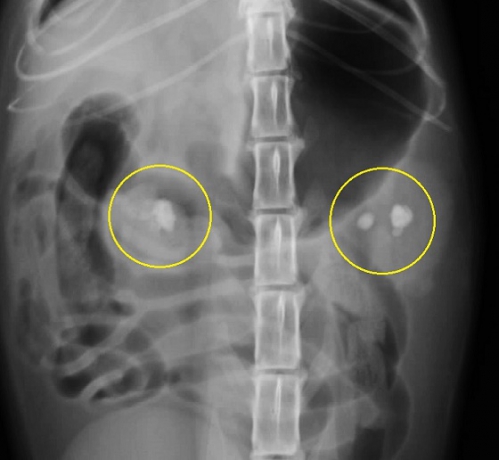

下の写真は両側の腎盂内に比較的大きな腎結石が発見された猫の腹部レントゲン写真です。上写真が縦方向下が横方向のものです。